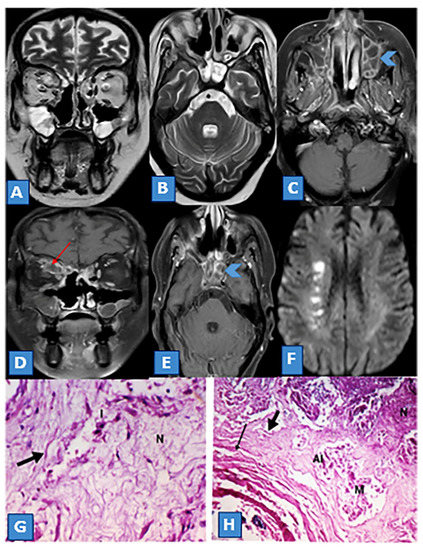

3.3. MRI Findings and Signal Characteristics

3.4. Extrasinus Extension

3.5. Histopathological Findings